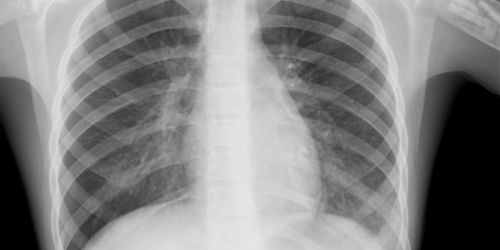

Пневмония (воспаление легких) – это воспалительный процесс, развивающийся в одном легком или двух одновременно. Чаще всего пневмония вызвана вирусами, грибками или бактериями. Чтобы назначить правильное лечение, необходимо выяснить, какой конкретно вид заболевания.

Симптомы пневмонии зависят от причин заболевания, а также от того насколько распространился процесс инфильтрации по тканям легких. По объему поражения различают пневмонию: очаговую, полисегментарную и долевую. Процесс может быть как односторонним, так и двусторонним. Среди главных симптомов: общая слабость, утомляемость, озноб, резкий рост температуры (38-40 градусов). Частым симптомом является сухой кашель (со временем он становится влажным, слизисто-гнойная мокрота тяжело отделяется. Если в процесс вовлекается плевра, при вдохе появляется болевой синдром. При тяжелом течении заболевания происходит одышка, есть бледность или синюшность кожи в области носогубного треугольника. В клинической картине симптомы интоксикации могут весьма преобладать, если пациенты – дети или люди пожилого возраста.

Важно. Пациенту необходима тщательная диагностика, чтобы не перепутать пневмонию с туберкулезом, поскольку симптомы идентичны.

Перед назначением терапии, направленной на лечение, пациент проходит полное обследование в условиях стационара. Если ставится диагноз воспаление легких, но нет температуры и кашля, необходимо исключить, например, туберкулез и онкологию.